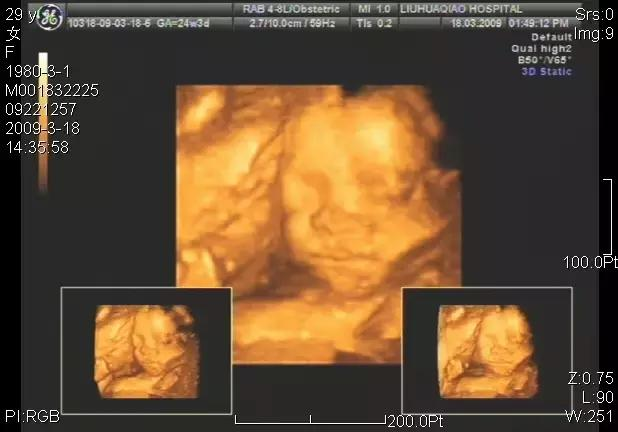

四、孕期"大排畸"B超

孕22~28周进行一次详细、系统的超声检测,排除胎儿大部分畸形,因此也称作"大排畸"B超。这个时段胎儿的肢体及各主要脏器已经全部发育,而且羊水较适合做胎儿畸形筛查。

目前业内规定产前超声筛查应该检查出的内容,包含如下:1、脊柱2、头颅3、面部4、心脏5、腹部6、四肢7、胎儿附属物

无论是二维、三维亦或四维彩超都只能对胎儿的大体结构进行筛查,也只有明显的结构畸形才能被发现。